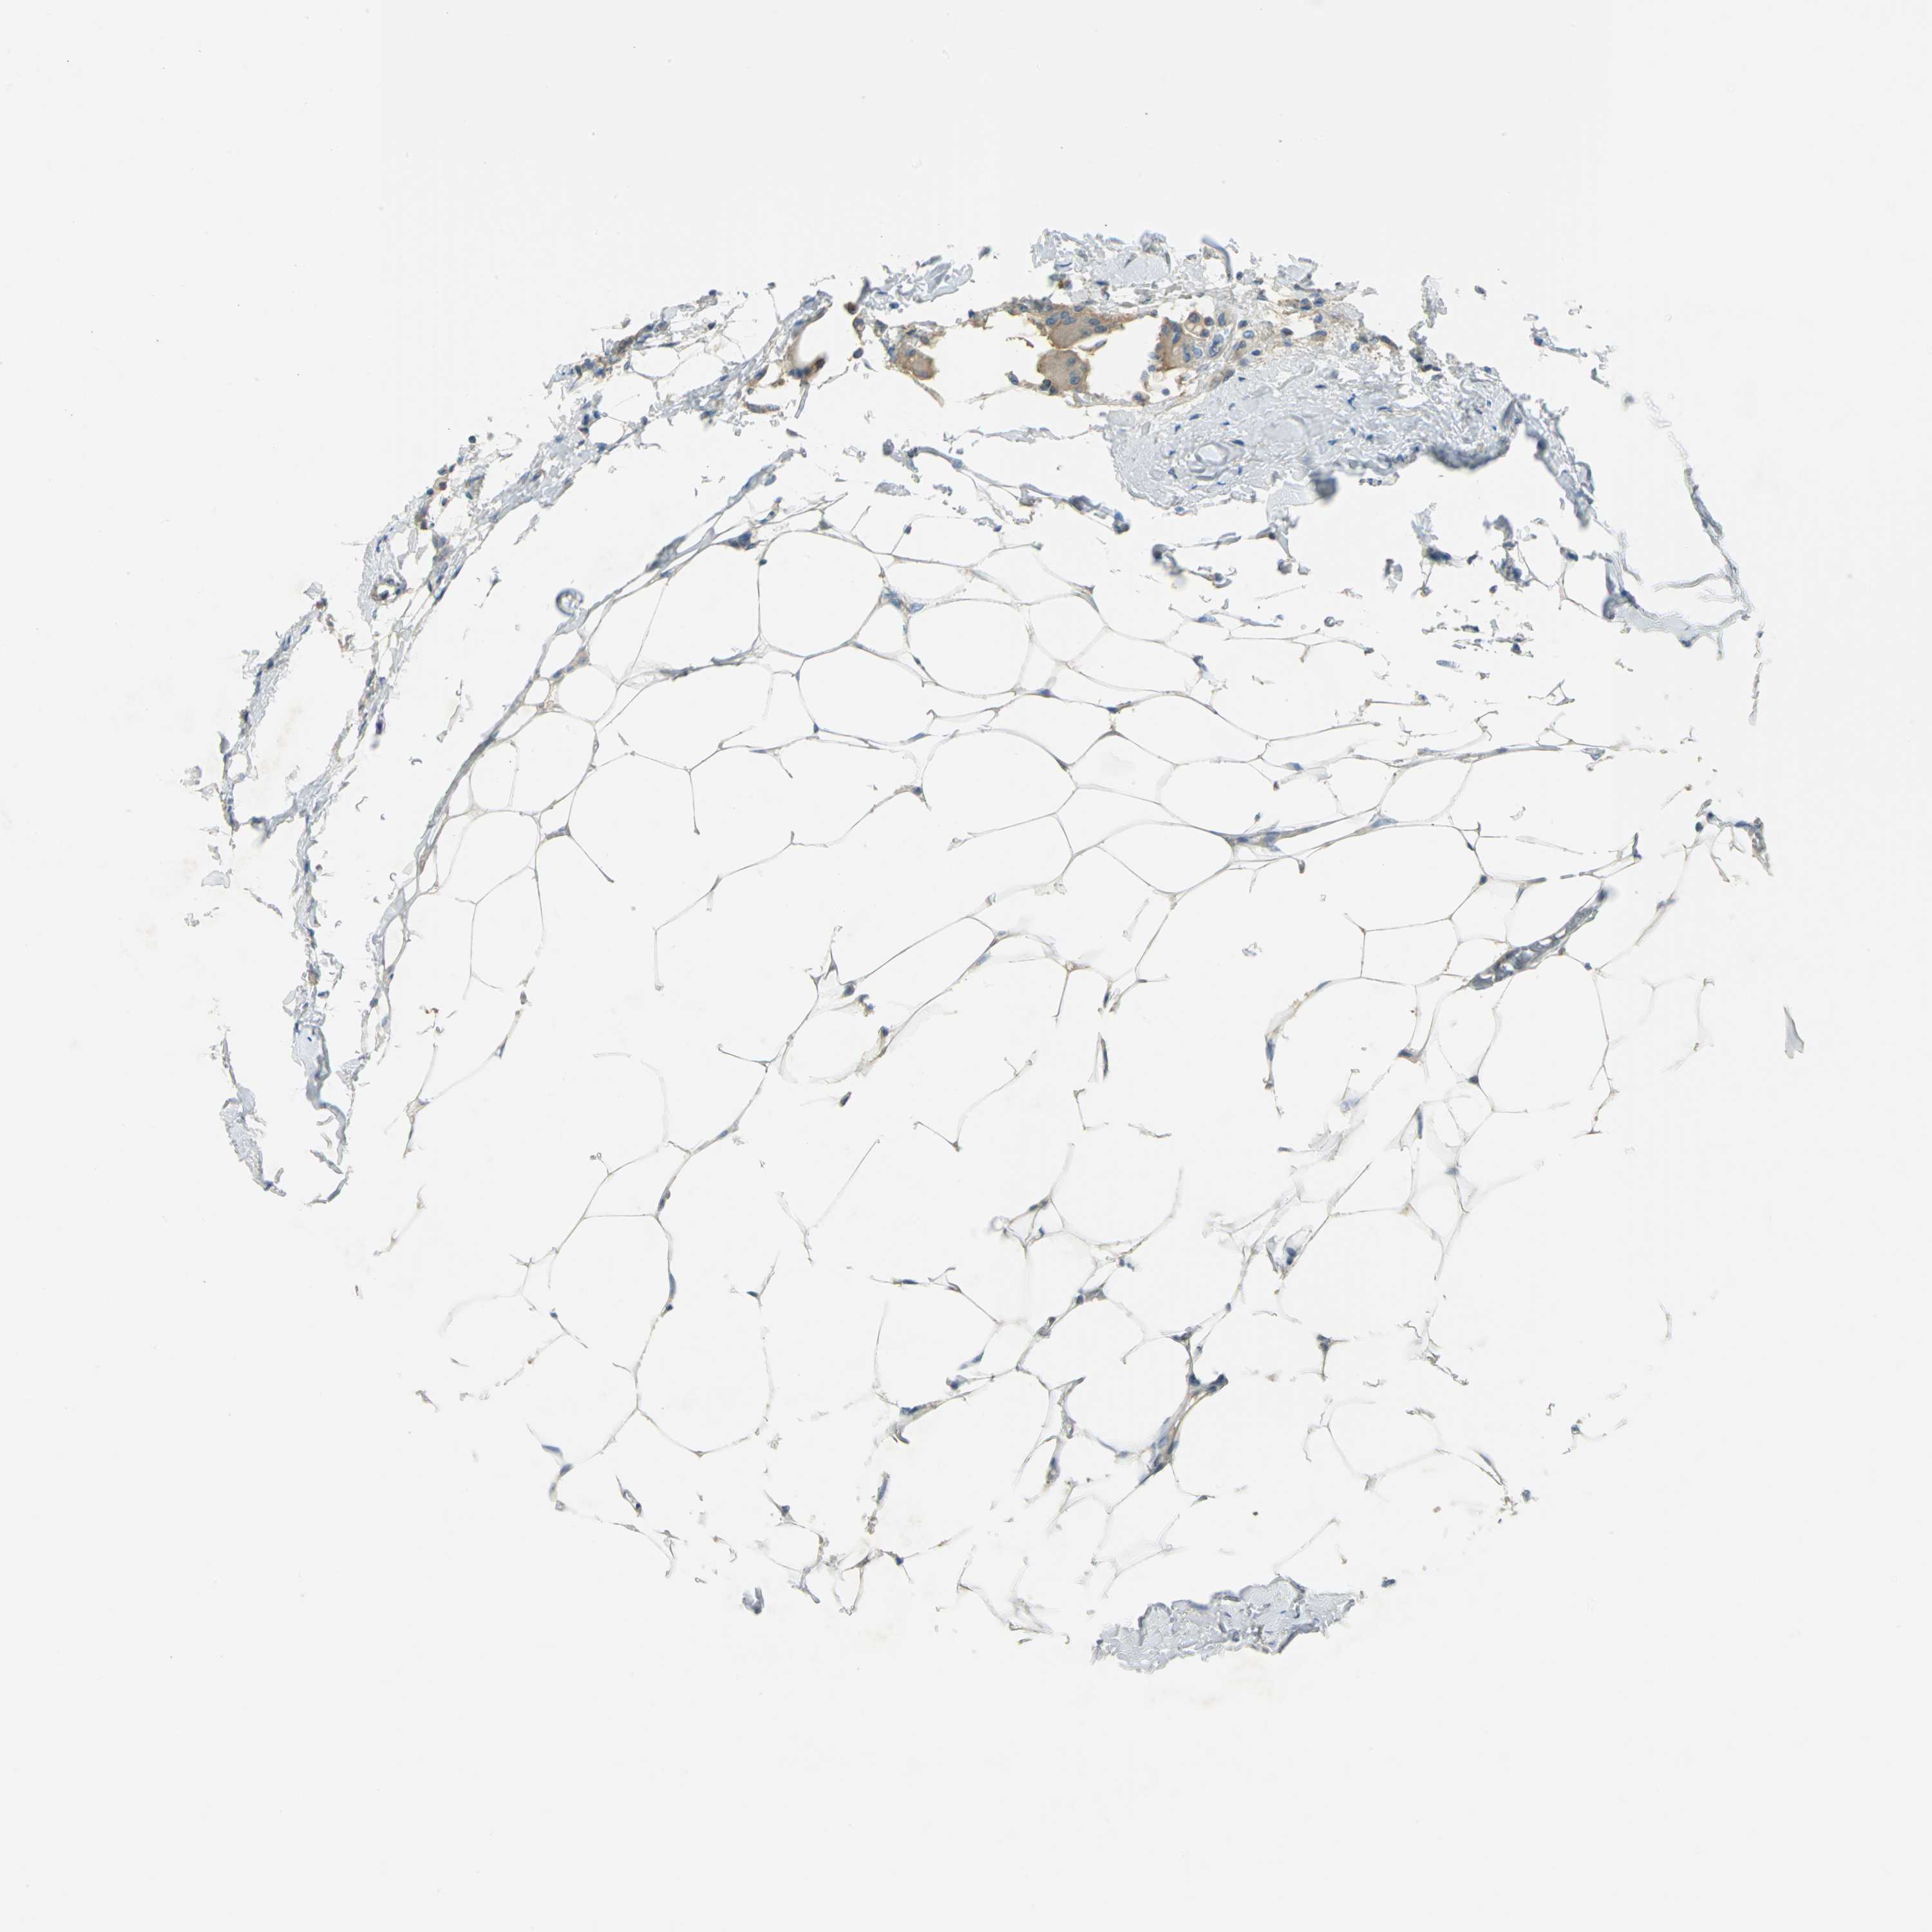

BRCA TCGA BRCA VALIDATION PROTEIN EXPRESSION

ANTIBODIES

AND

VALIDATION